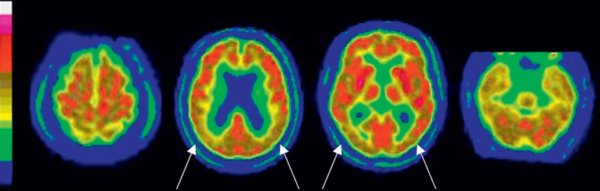

Figure 23.3

Exemple d'un aspect normal en TEP cérébrale au 18F-FDG en coupe axiale.

À gauche, l'échelle de couleur suivie des coupes axiales d'une TEP normale en partant du sommet du crâne à gauche vers le bas du crâne à droite. Le cortex cérébral, le striatum (flèches jaunes) et les thalami (flèches blanches) présentent une fixation homogène qui apparaît en rouge, de même que les deux hémisphères cérébelleux (étoile).